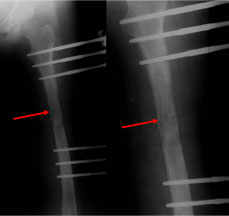

These x-rays show the progress of consolidation. The regenerate solidifies into stronger bony tissue during this process.

The criteria for removal of the fixator is formation of at least three cortices (out of four-anterior, posterior, medial & lateral). The fixator is removed after gradual disassembly. First the CD unit is removed and clamps are loosened. Patient is then asked to walk for about 10-15 minutes. If there is no pain or trouble then the next step is to remove the rail and clamps, the schanz screws remain in position. Again the patient is asked to walk for 10-15 minutes. Once this step is done comfortably, the schanz screws are removed usually in the out patient department itself. |

In this particular case, when the patient was made to walk during the second stage of fixator removal i.e. after the rail and clamps were removed, there was pain after a few steps. The LRS assembly was reapplied connecting the clamps with rail and fresh x-rays taken.

The radio-lucent line seen here (red arrow) in the middle of the regenerate depicts the fracture in the regenerate. This is a known complication and is seen rarely. The further treatment is to continue with the fixator till union, which generally takes 8-10 weeks. During this time the patient continues to bear full weight. |